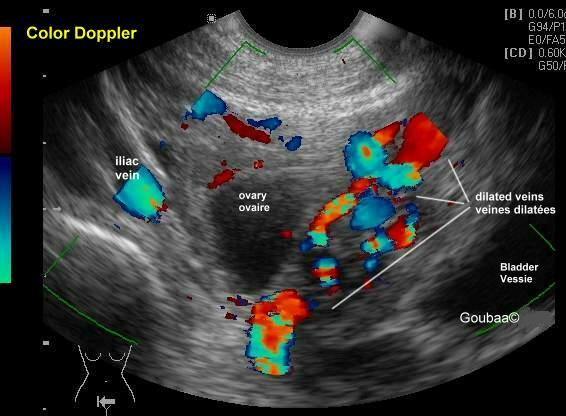

顾名思义,不过是盆底静脉迂曲扩张,由于在深处,只有少部分患者会有会阴、臀部及大腿静脉曲张的外在表现,单纯静脉曲张还好,对生活质量影响小,如果曲张严重就会产生一系列的临床表现,尤其是慢性的腹部不适,医学上有术语叫做盆腔瘀血综合征。

盆腔淤血综合征其实是盆腔曲张基础上出现,而盆腔的静脉丛特别丰富,曲张最为多发的是左侧的卵巢静脉。左侧容易出现曲张的原因主要是因为人体特殊的解剖构造所决定的,而女性更为高发则是因为怀孕过程增加了本病的发生机会。男性当然也有,只是比较少见,主要表现出精索静脉曲张。

静脉造影虽然属于金标准,但是毕竟有创伤存在,不适合进行病人的筛查。而超声因为其无创性,是一个很有效的筛查手段,可以提供血管的动态指标,提示血管的直径和流速,但是对超声医生的要求比较高。CT和核磁检查呈现比较立体,更受青睐,需要体内注射一些对比剂。当然也有一些报道会采用腹腔镜探查的方式来判断,但是单纯因为可耐受的慢性腹痛去做这个手术,并不受待见。